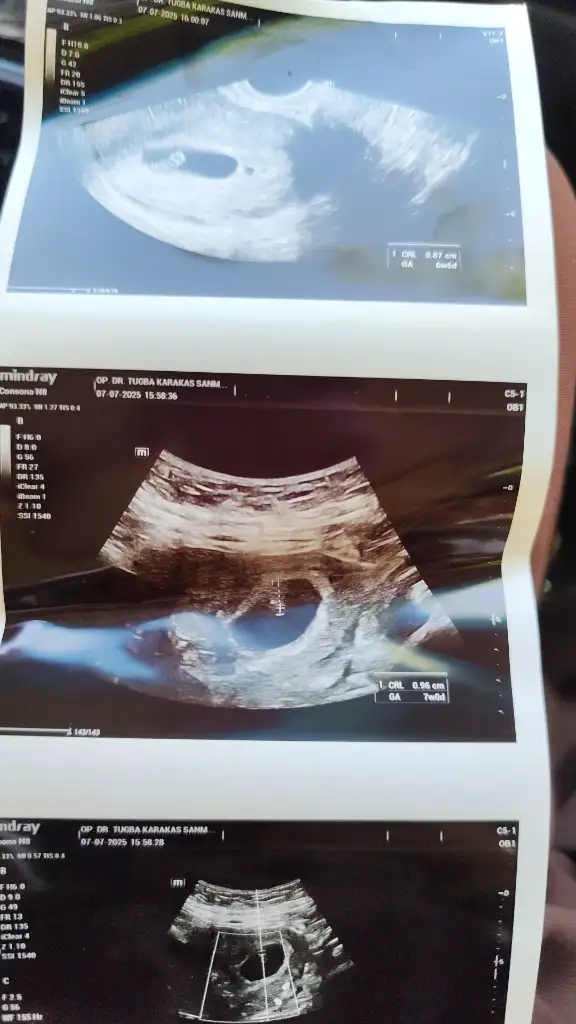

U Umay_00 Yeni Üye Kayıtlı Üye 15 Mart 2025 41 9 1 20 30 Haziran 2025 Konu Sahibi Konu Sahibi Umay_00 #1 Keseye duruşuna göre cinsiyet tahmini yaparmısınız

I incim1 Aktif Üye Kayıtlı Üye 21 Ekim 2024 3.092 808 43 28 30 Haziran 2025 Konu Sahibi Konu Sahibi Umay_00 #2 Umay_00 .!.: Keseye duruşuna göre cinsiyet tahmini yaparmısınızEki Görüntüle 3611489 Genişletmek için tıkla... Kız bence

Umay_00 .!.: Keseye duruşuna göre cinsiyet tahmini yaparmısınızEki Görüntüle 3611489 Genişletmek için tıkla... Kız bence